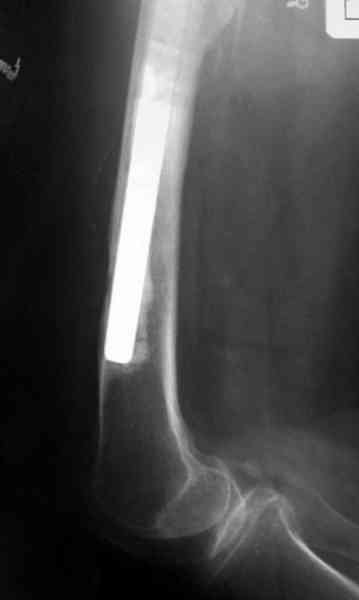

Для спейсера в бедро использовал старый длинный бедренний компонент меньшего диаметра, облепленный со всех сторон цементом с антибиотиком.

Наглухо ушитая рана с дренажом зажила первично, после чего с больной потерял контакт, и только недавно, через 8 лет я осмотрел её. Она без проблем нагружает на конечность и передвигается с помощью трости. От окончательной операции по реконструкции отказывается, довольная результатом.

Имеются литературные данные, когда спейсер держали не более 6 месяцев, но этот случай бьет все рекорды, может быть для наших людей, обременных финансовыми трудностями, нужна другая шкала оценки сроков нахождения спейсеров.

и последние снимки.